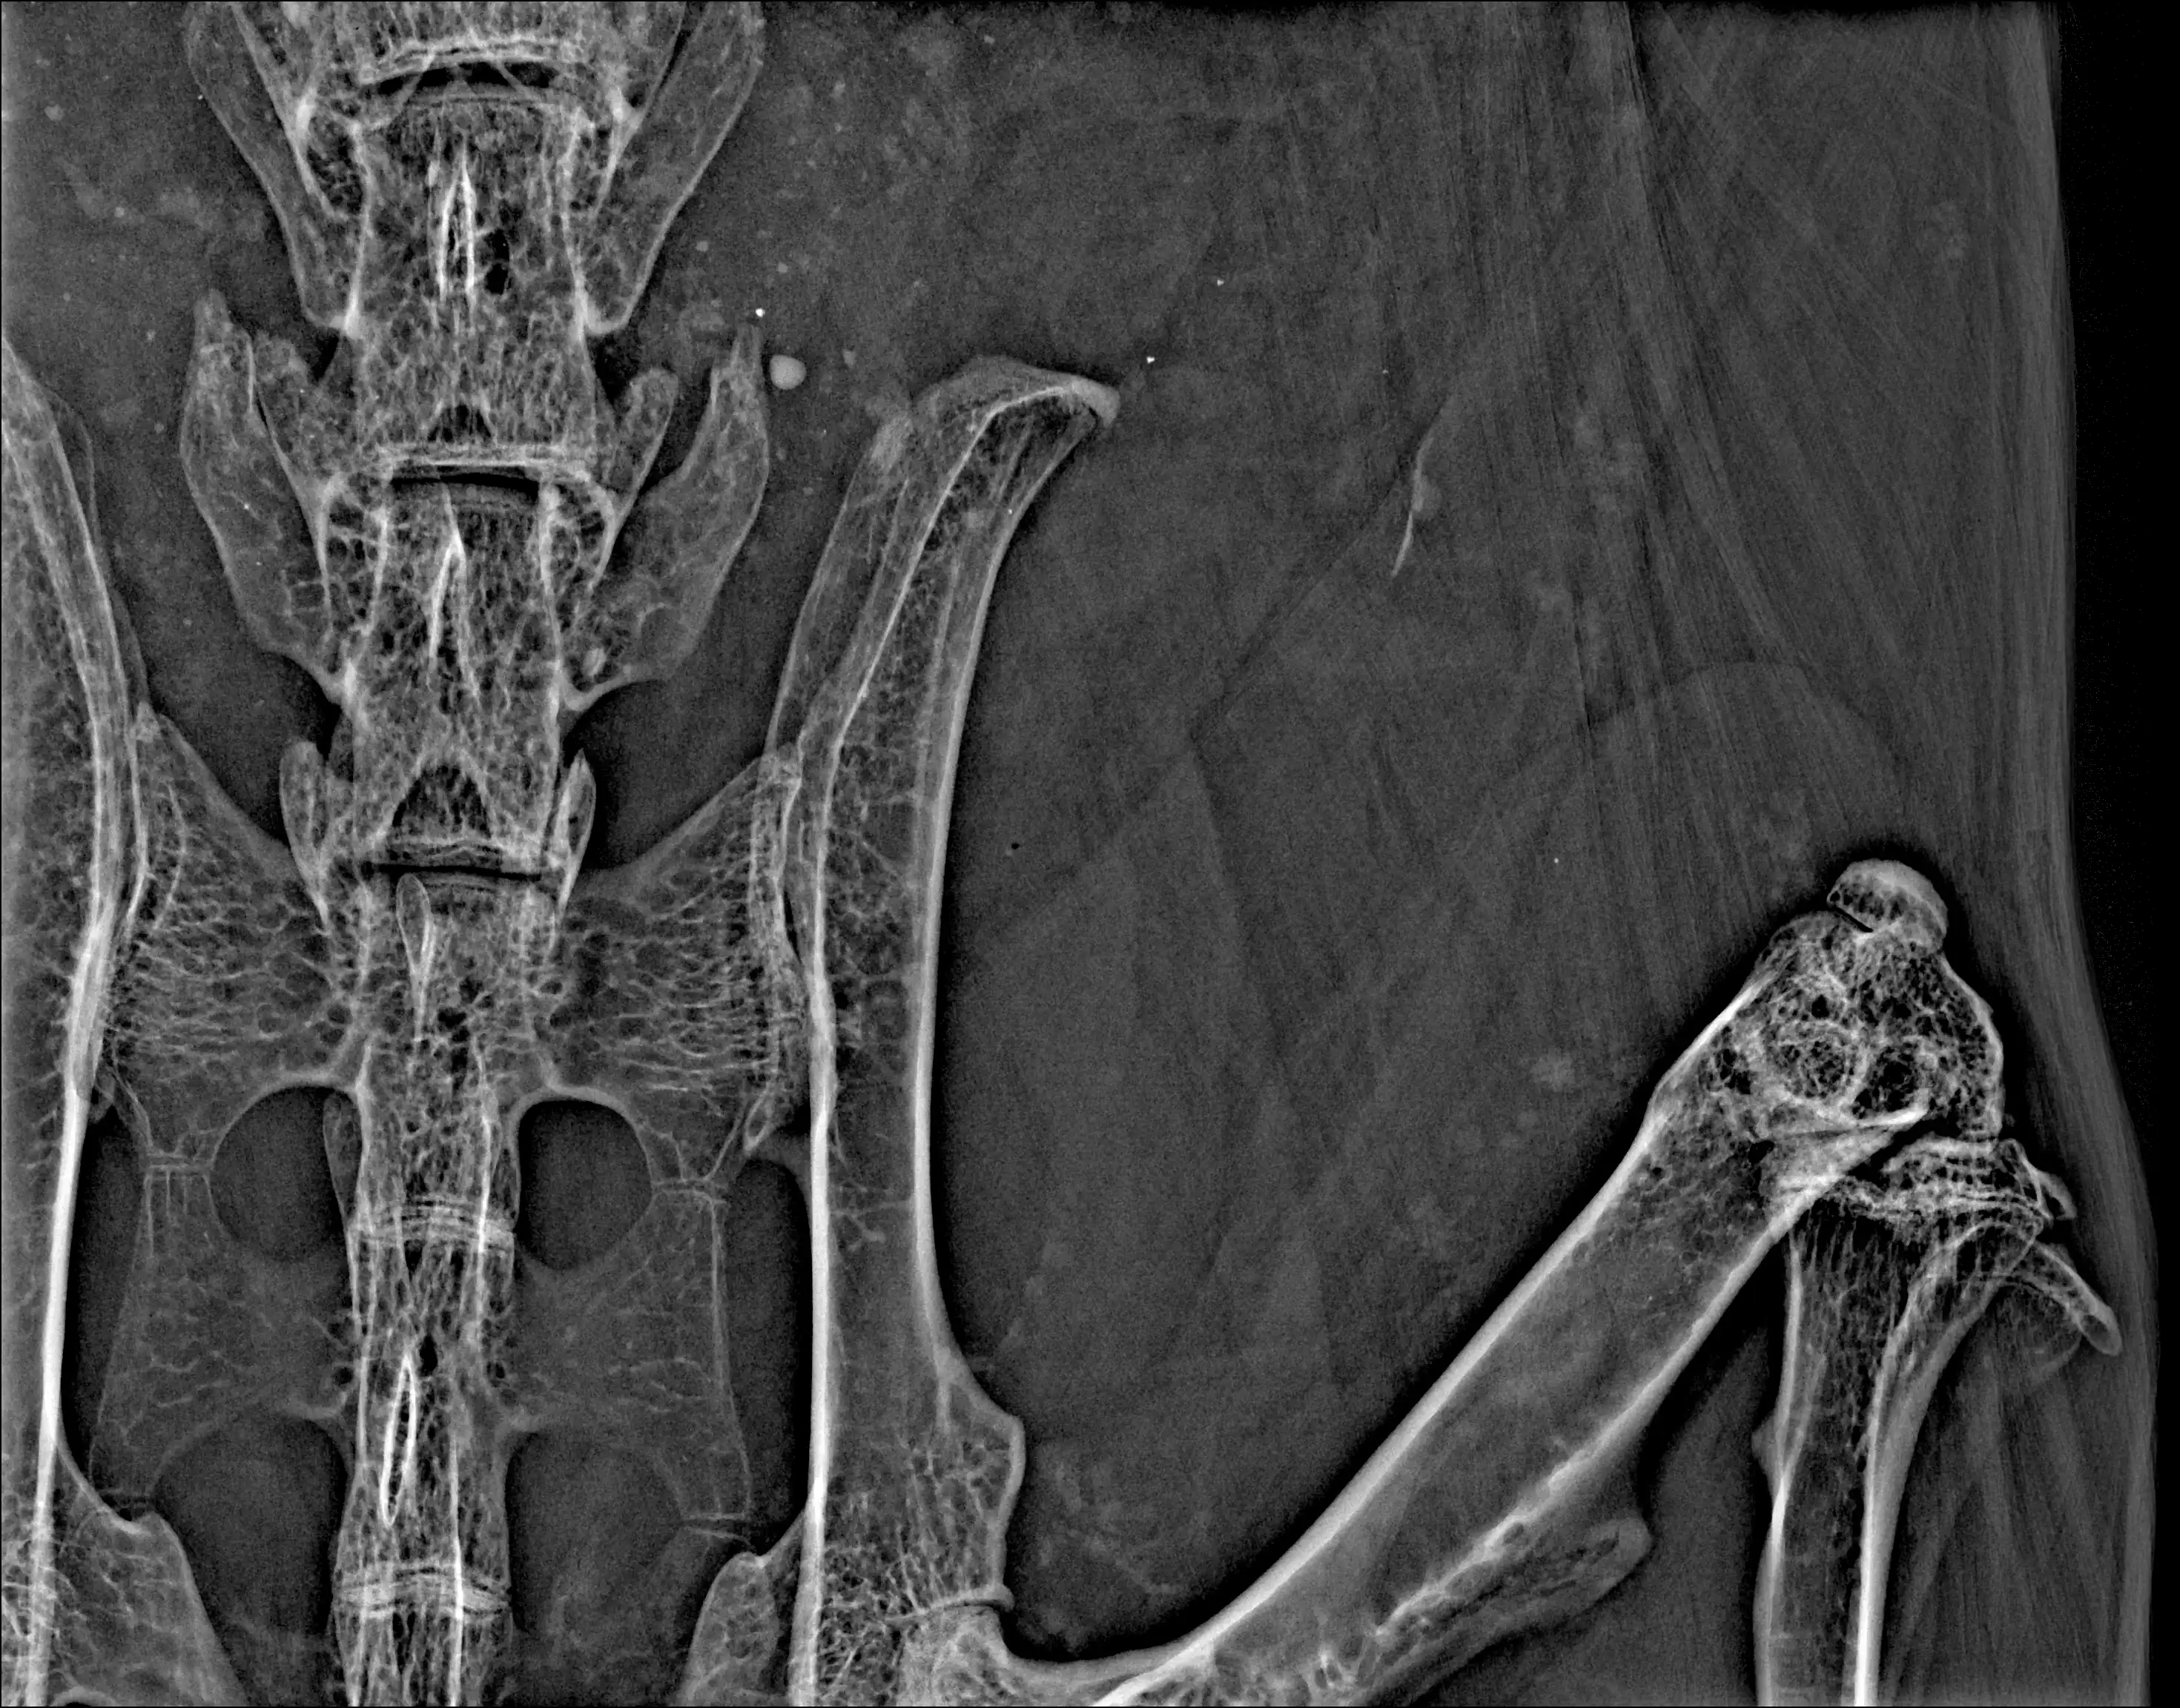

The PARAMETER and XPERT product families capture high-resolution X-ray and optical images in stunning detail with spatial resolution down to <50 µm.

With KUBTEC systems, users can identify morphological and anatomical changes in bone and soft tissue in a range of animal research models, enrich comprehensive longitudinal datasets, and take geometric and densiometric measurements directly in-software.